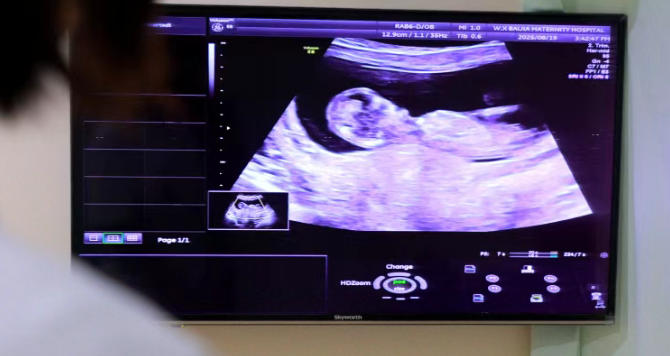

NT(颈项透明层)检查是孕早期一项重要的超声筛查,通常在孕11周~13周+6天进行。

它主要通过测量胎儿颈后透明层的厚度,并结合其他指标(包括鼻骨是否可见等),来评估胎儿是否存在某些染色体异常或结构问题的风险。